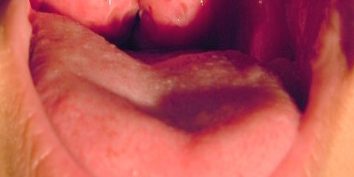

Tonsils are mass of tissue on both sides of the throat that help fight infections. Tonsils may enlarge when they become infected (tonsillitis). the tonsils may be red and swollen or have a white or yellow spots or coating on them. Other symptoms of tonsillitis can include

Enlarged tonsils without any symptoms are common among kids. No treatment is required if no symptoms. Don’t rely on your own guesses, it can be hard to judge whether tonsils are infected. If you suspect tonsillitis, contact your doctor. Recurrent sore throats and infections should also be evaluated by the doctor.